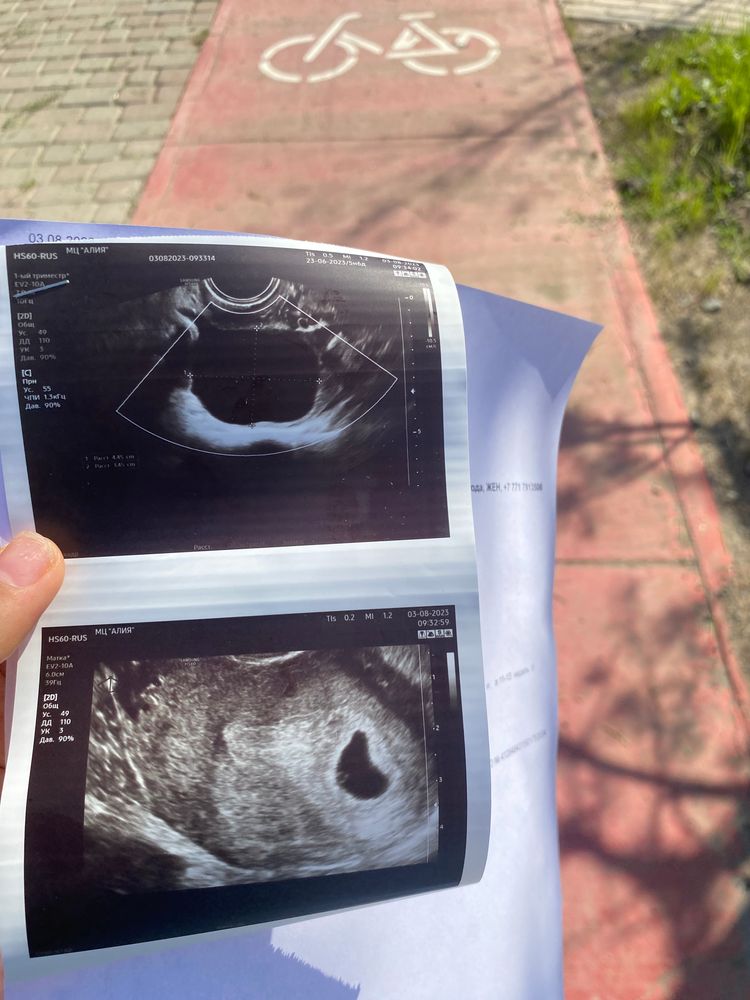

Здравствуйте, дорогие.Сегодня была на узи акушерский срок 5нед и 6 дней. Говорят, что неправильной формы плодное яйцо и эмбрион не видно.возможно не развивается. Соответствует 5 неделям((Овуляция была поздняя на 29-20дц. Хгч растет тьфу тьфу хорошо. 1 августа на 21 дпо хгч 6670. Сегодня (3 августа) пришла на контрольное узи, так как неделю назад был точечный фрагмент напоминающий ПЯ. Сегодня такое говорят. Приходите в 7 недель. Я так переживаю. У меня ещё неделю назад была киста желтого тела слева 56 мм, сегодня на узи отметили кисту справа 44мм. Не пойму ( Я так волнуюсь, не смогу ждать ещё неделю🥵😭я так ждала малыша

Рано для эмбриона,темболие овуляция поздняя,у вас получается УЗИ 23 дпо,я на 22 дпо ходила пя 8 мм,жм 1,6 никакого эмбриона в помине не было,на 31 дпо повторно пя 19 мм,ктр 5,4 и ЧСС 146 уд/мин